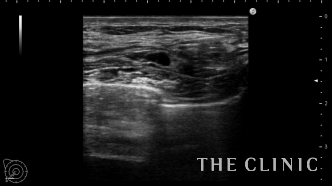

エコーで確認するとかなり厚い被膜が形成されています。

アクアフィリングは生理食塩水で溶解されるとのことで、エコー下に生理食塩水を注入しました。

なかなか溶解できず、ヒアルロニダーゼも追加してなんとか溶解除去することができました。